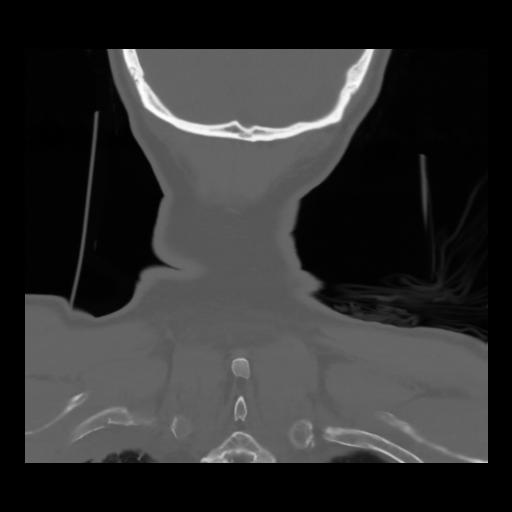

13 P.BLANDAS,,Coronal,2.000,P.BLANDAS,Coronal,